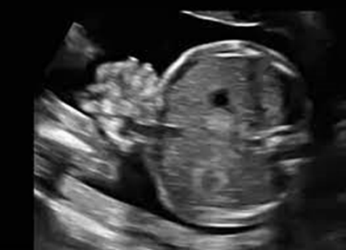

Uma gestante realizou ultrassonografia morfológica com vinte e duas semanas de gravidez. Durante a realização do exame, foi evidenciada a imagem seguinte. O achado ilustrado na imagem foi encontrado isoladamente.

Com base nesse caso hipotético, assinale a alternativa correta.